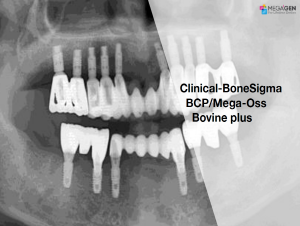

e.g. product name, treatment solution, author, clinician name